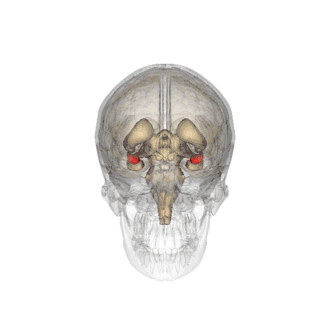

Divisiones anatómicas

Amígdala izquierda en rojo, visible en un corte vertical de una resonancia magnética.

Las regiones descritas como «amígdala» en realidad abarcan una serie de núcleos con distintos atributos funcionales llamada complejo amigdalino. Entre esos núcleos se encuentra el grupo basolateral, el núcleo centromedial y el núcleo cortical. El grupo basolateral se puede dividir a su vez en el núcleo lateral, el basal y los núcleos basales accesorios.[2][4]